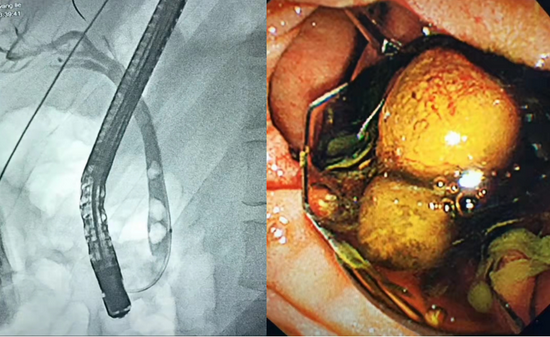

这是一封略显啰嗦的感谢信。但是唯有啰嗦才能详尽表达我的感激之情。非常感谢贵院普外二科主任张双卫先生及其医疗团队对我的诊治,正是贵院这群如张主任般杏林春暖的医生造福了故乡万千的病患。遥祝贵院高擒智慧之火炬,永筑健康之光芒,同时祝福张双卫主任及医院同仁阖家幸福,万事胜意。